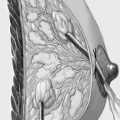

The segment containing the tumor is dissected sharply with dissecting scissors or electrocautery to obtain an initial adequate resection margin under digital control or sonographic direct visualization.

The segment containing the tumor is dissected sharply with dissecting scissors or electrocautery; an adequate initial resection margin should be obtained under digital control or sonographic direct visualization. A specimen sonogram or mammogram is performed when needed.

The adjacent parenchyma is mobilized subcutaneously so that the defect can be filled with lobes of breast tissue. Mobilization means exposing the breast relative to the skin or muscle to achieve adequate mobility of < 25% or > 25% as required.

To cover the defect, the glandular lobes are mobilized from the adjacent parenchyma after subcutaneous dissection. The principle of intramammary lobe creation is to mobilize large parts of the breast (> 25%) either relative to the skin or relative to the pectoralis muscle. This “liberation” of the breast from one of its two planes of fixation allows adequate dissection and rotation of sufficient breast tissue. The Y-flap and rotation flap shown in Chapter 3.2.1 are examples of intramammary dissection.

When the breast is mobilized subcutaneously, it must be ensured that both the dissected skin layer and the breast tissue are sufficiently thick. For the layer of breast tissue, a minimum thickness of 1 cm is desirable. The ratio of base to length must also be considered.